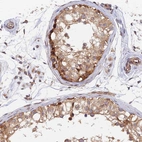

Immunohistochemical staining of human testis shows moderate to strong cytoplasmic positivity in cells in seminiferous ducts.